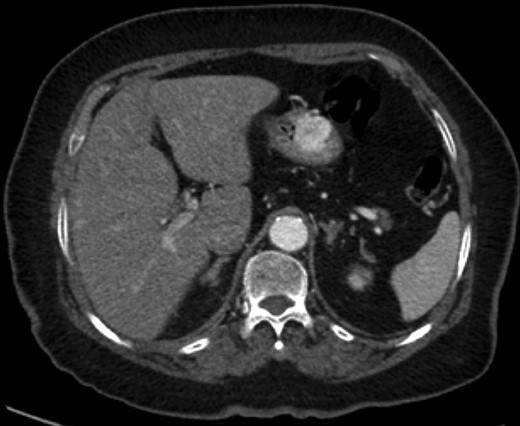

Grossly, GTs are multinodular, soft and rubbery on sectioning [3]. The cellular nodules are separated by streaks of gastric smooth muscle, which also surrounds the tumor [3]. Histologic features are central round to oval nuclei with inconspicuous nucleoli and clear to eosinophilic cytoplasm with distinct cell borders [1] (Figs. 3 and 4). GTs are positive for α-smooth muscle actin, vimentin, calponin and caldesmon. They are most often negative for CD117, CD34, chromogranin and synaptophysin [3, 6].

Gastric GT. Note central round or oval nuclei with clear, eosinophilic cytoplasm (H&E stain, ×200).